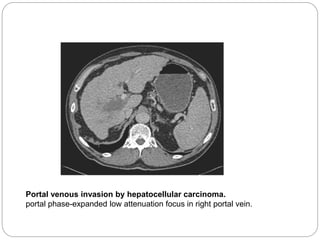

Hepatocellular Carcinoma Radiology